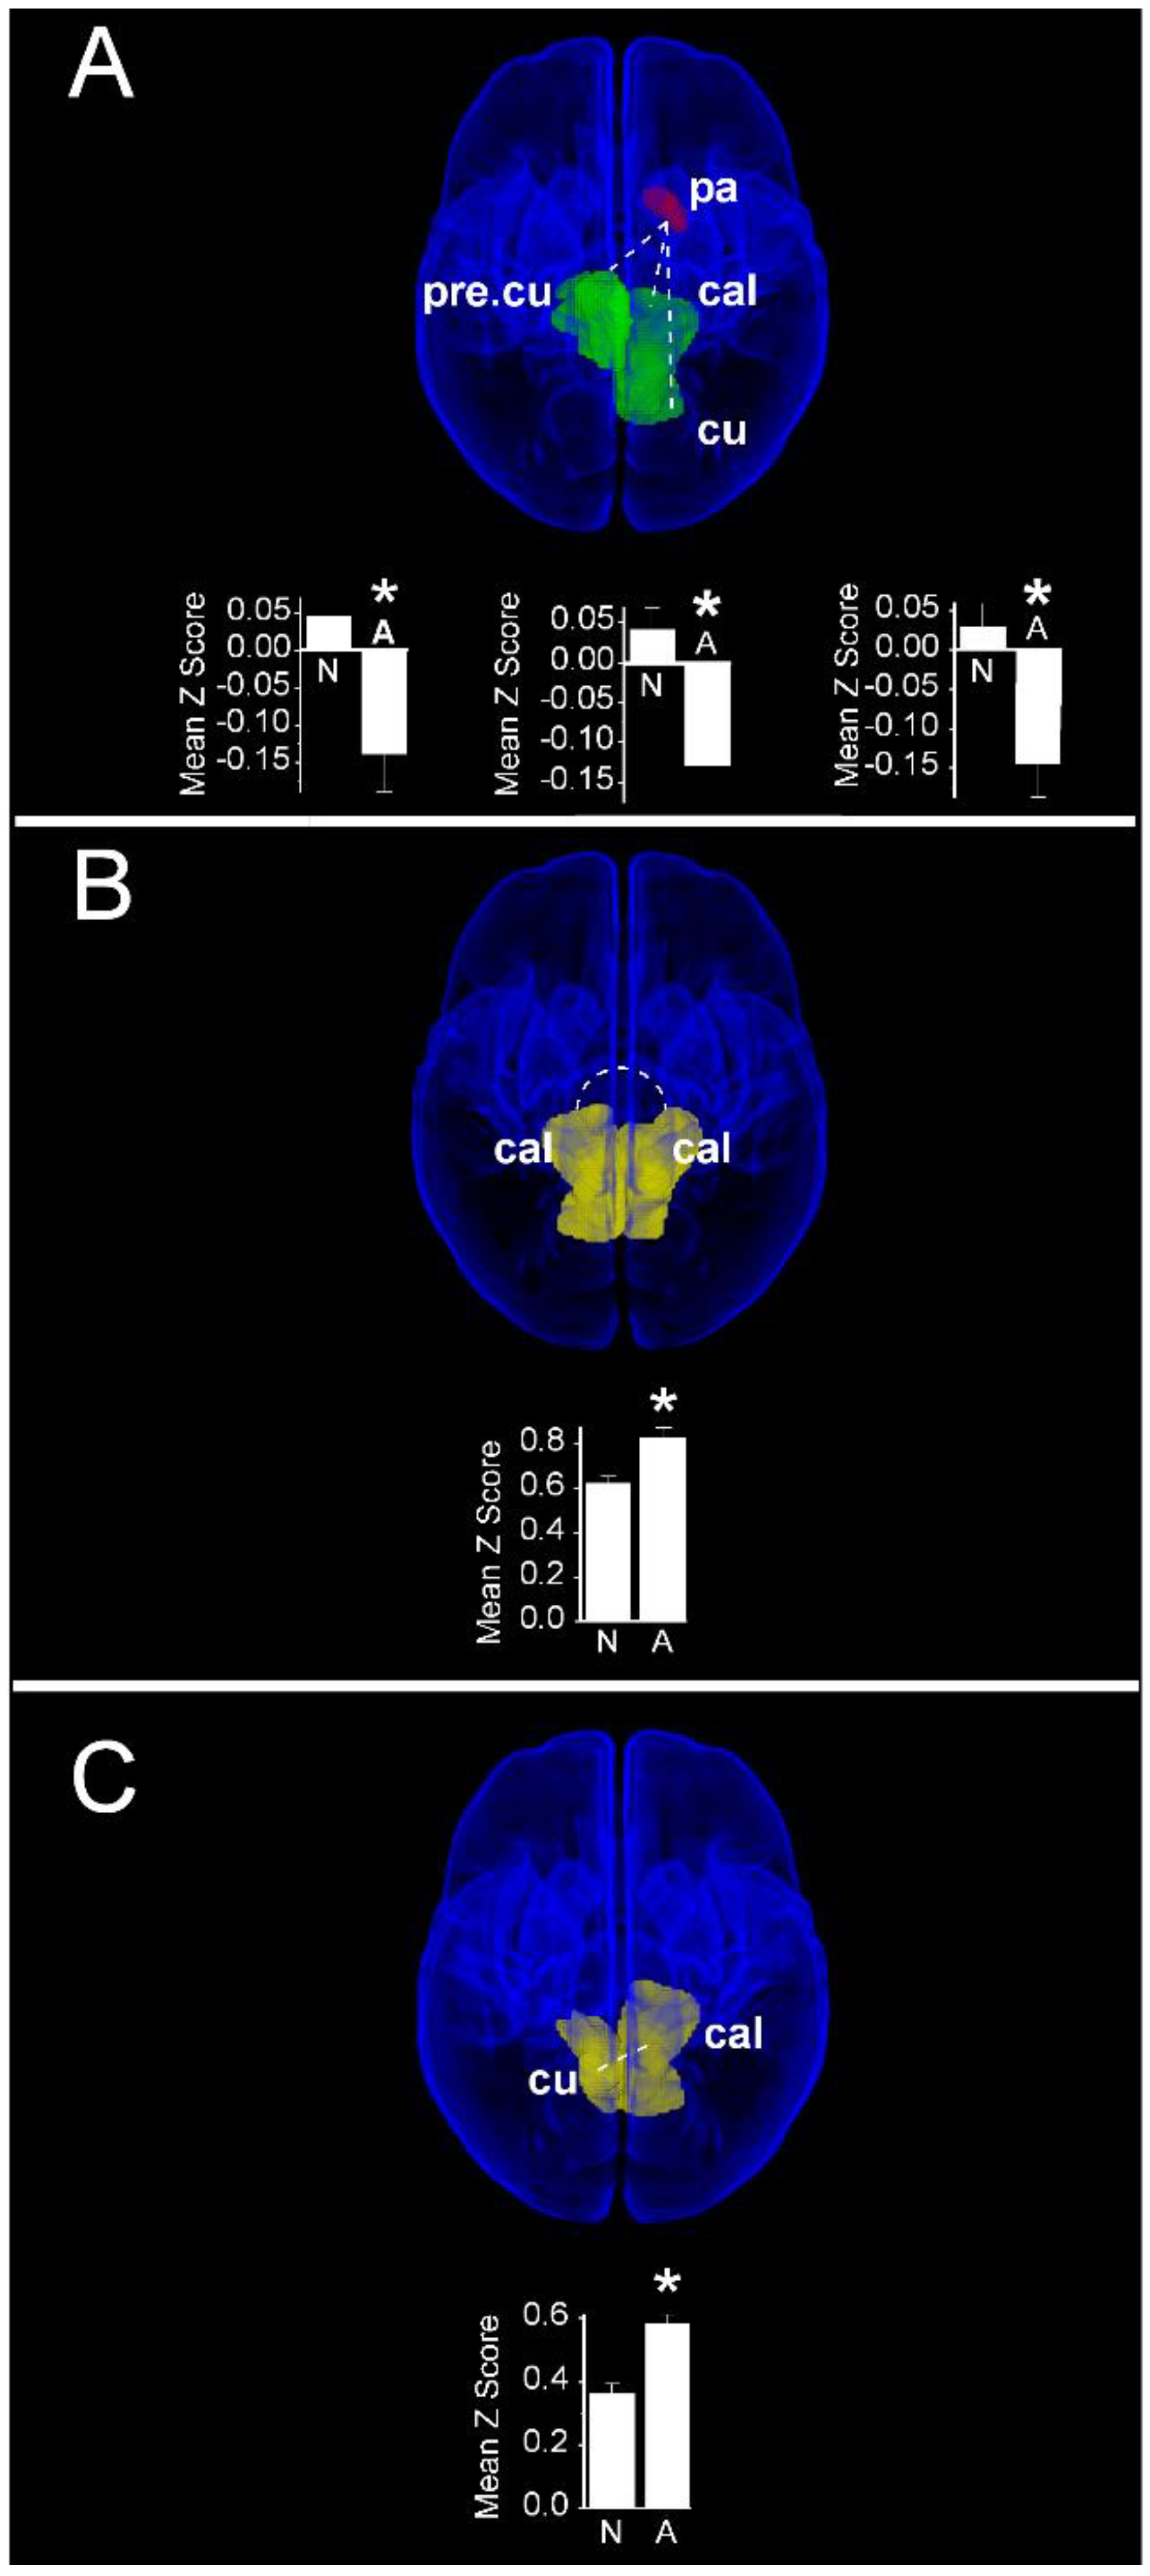

In contrast to cognitive scores, increased functional connectivity in infants with normal motor scores compared with those having abnormal motor scores were restricted to interactions between the left pallidum and vision-related cortical regions (Figure 8A). Compared with children with abnormal motor scores, infants with normal motor scores demonstrated a greater functional connectivity between the left pallidum and each of the right precuneus (Normal: 0.05 ± 0.03 vs. Abnormal: −0.14 ± 0.05; PFDR = 0.015), left cuneus (Normal: 0.03 ± 0.03 vs. Abnormal: −0.14 ± 0.04; PFDR = 0.015), and left calcarine cortex (Normal: 0.04 ± 0.03 vs Abnormal: −0.13 ± 0.04; PFDR = 0.018). Notably, these infants also demonstrated a weaker functional connectivity compared with children having abnormal motor scores between bilateral primary visual (calcarine) cortices (Normal: 0.62 ± 0.03 vs. Abnormal: 0.83 ± 0.05; PFDR = 0.018, Figure 8B), as well as between the left calcarine and the contralateral cuneus cortex (Normal: 0.36 ± 0.03 vs. Abnormal: 0.59 ± 0.05; PFDR = 0.018, Figure 8C). Finally, we observed no significant differences in functional connectivity when infants with normal and abnormal language scores were compared.

Figure 8. Region pairs exhibiting increased and decreased functional connectivities in infants with normal (≥85) and abnormal (<85) scores on the motor subscale of the Bayley III assessment at two years post-menstrual age. Obliquely projected 3D reconstructions of MRI images of cerebral grey matter and identified parcellated regions derived from a neonatal atlas. Dashed white lines depict connectivity relationships. Inset: Fisher-transformed Z-scores ± 1 SEM. (A) Increased connectivity between pallidum and visual cortex regions: left: left pallidum and contralateral precuneus; middle: Left pallidum and ipsilateral calcarine cortex; and right: Left pallidum and ipsilateral cuneus. (B) Decreased connectivity between bilateral calcarine cortices; (C) Decreased connectivity between left calcarine and right cuneus. N: Normal; A: Abnormal. * PFDR < 0.05.